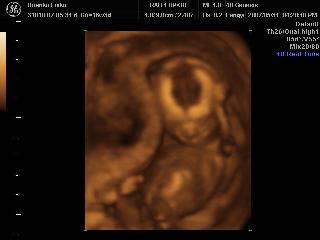

Karcsika 16 hetesen

Most [/img]